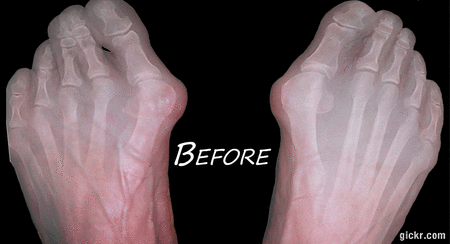

Tag: bunion

bunion